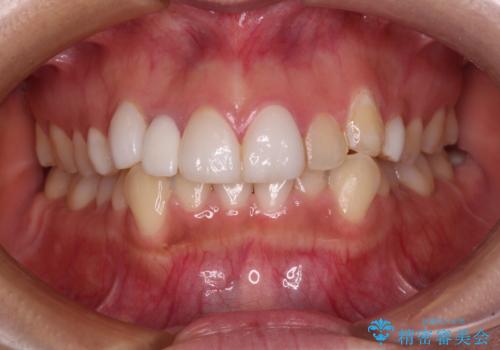

[ 総合歯科診療 ] がたつきの改善とセラミック治療

![[ 総合歯科診療 ] がたつきの改善とセラミック治療の症例 治療前](https://seimitsushinbi.jp/wp/wp-content/uploads/2024/03/f0f438a14c56b185411649f48b5b188c-500x350.jpg?v=1710833163)